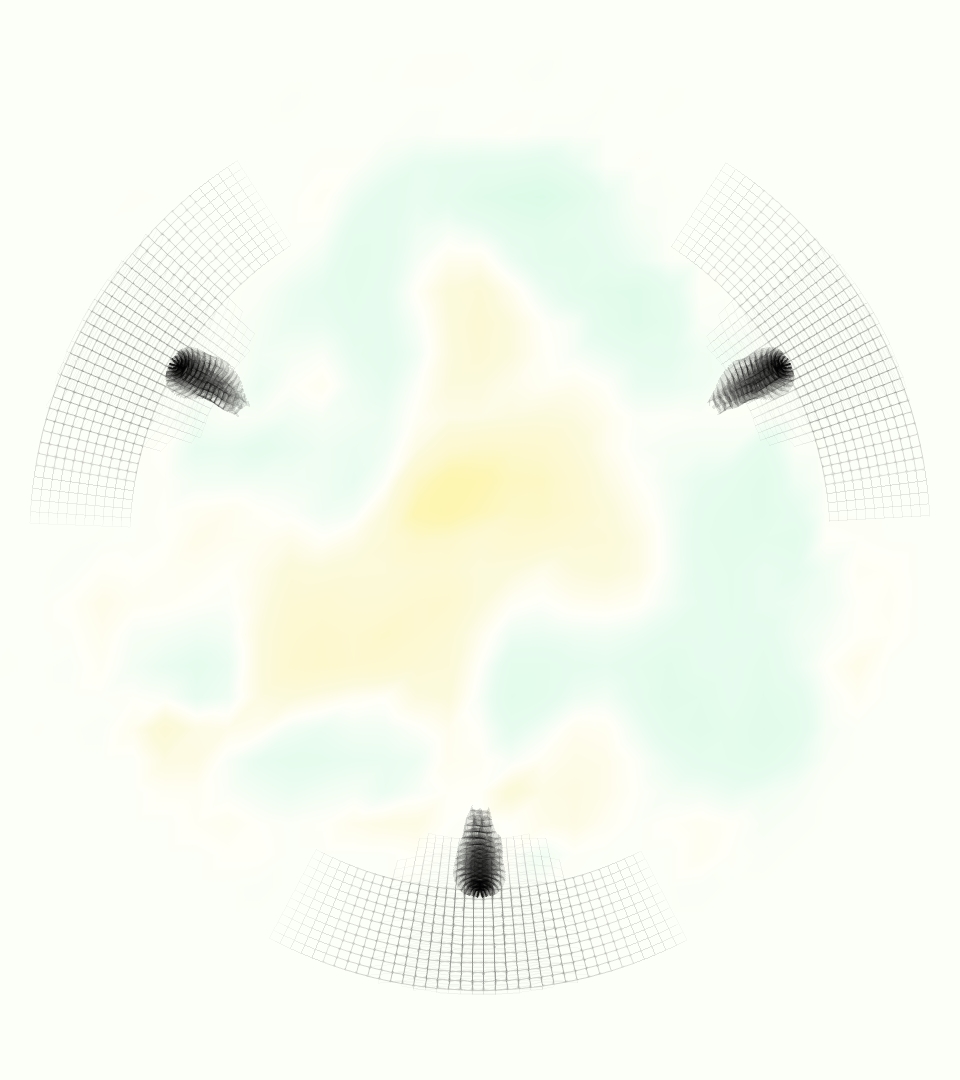

A comparison between the phase-averaged velocity resampled onto the MRI grid, the phase-averaged velocity without resampling, the instantaneous flow field without resampling and the MRI velocity field is shown in Figure 8. The coarser resolution is visible as a “stair-stepping” or “pixelated” effect on the phase-averaged resampled velocity, whereas the edges of the jet are more smooth in the phase-averaged velocity with no resampling. Otherwise, the resampled velocity appears qualitatively similar to the phase-averaged velocity with no resampling. Fine scale features were present in the instantaneous field that were lost in the phase-averaging and resampling process. There was more variation in the local velocity of the center of the jet and local areas of high velocity at the edges of the jet that suggested vortices. Vortical structures adjacent to the jet and in the areas of reversed flow were apparent. These comparisons suggest that 4D flow MRI data may lose substantial fine-scale flow features in the flow field via phase-averaging.

Of potential future interest, the phase-averaged, resampled velocity showed substantial differences from the instantaneous velocity fields, with more variation in local fluid velocity and more fine scale vortical structures visible in the simulation (Figure 8). This points to an advantage for simulations: since 4D flow MRI data is fundamentally phase-averaged, once validated, simulations provide a richer dataset when these instantaneous fluid features are of interest.